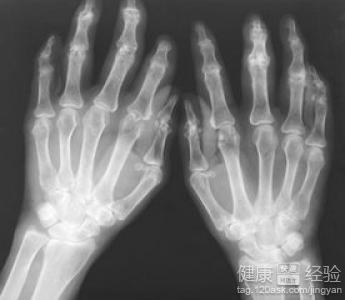

類風濕性關節炎是人體的自身免疫病。現在人很多都會出現類風濕性關節炎。關節炎會在關節處產生痛感,尤其是在活動的時候會劇烈疼痛。這是在早期出現的症狀。類風濕性關節炎的患者大多數都會感到疼痛,腫脹,僵硬,甚至是畸形。所以大多數人都會選擇用藥治療。所以在治療期間會有很多禁忌,比如有些,蔬菜,食物不能食用。當然相反也會有些食物有利於類風濕性關節炎的治療。

類風濕關節炎的飲食吃什麼東西好